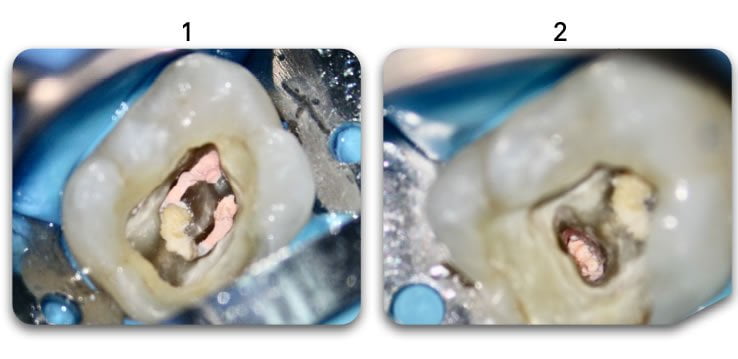

YES. Biolight® DRILL-FREE provides a solid, anatomical anchoring to remaining tooth structure. By arranging reinforcement towards the periphery of the canal walls, support of the core is improved. The concept is similar to how reinforcement steel rods and used in concrete structures, where many smaller rods are placed around the perimeter of the concrete. In addition, all risks associated with drilling are eliminated.

YES. At first glance, Biolight® DRILL-FREE appears to be perfectly adapted for use in oblong canals, however, since the concept behind the product is to provide support around the periphery of the canal walls, it is ideal for ALL shapes of canals.